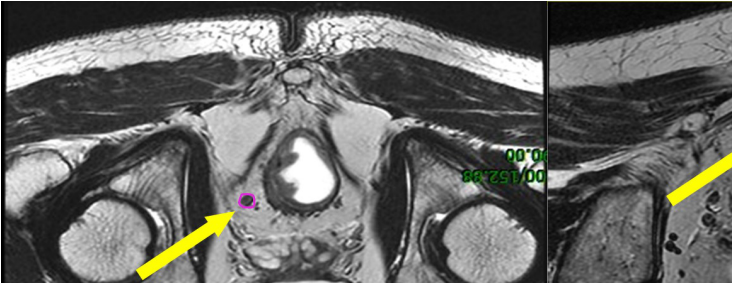

b) GTVnd(粉色) :轉(zhuǎn)移淋巴結(jié)在診斷磁共振或定位磁共振圖像顯示清楚,可參考并輔助在 CT 定位圖像完成 GTVnd 的勾畫(圖 2-圖 4)。

圖 2 直腸癌俯臥位直腸系膜區(qū)淋巴結(jié)勾畫示例

圖 3 直腸癌俯臥位骶前區(qū)淋巴結(jié)勾畫示例

圖 4 直腸癌俯臥位淋巴引流區(qū)淋巴結(jié)勾畫示例